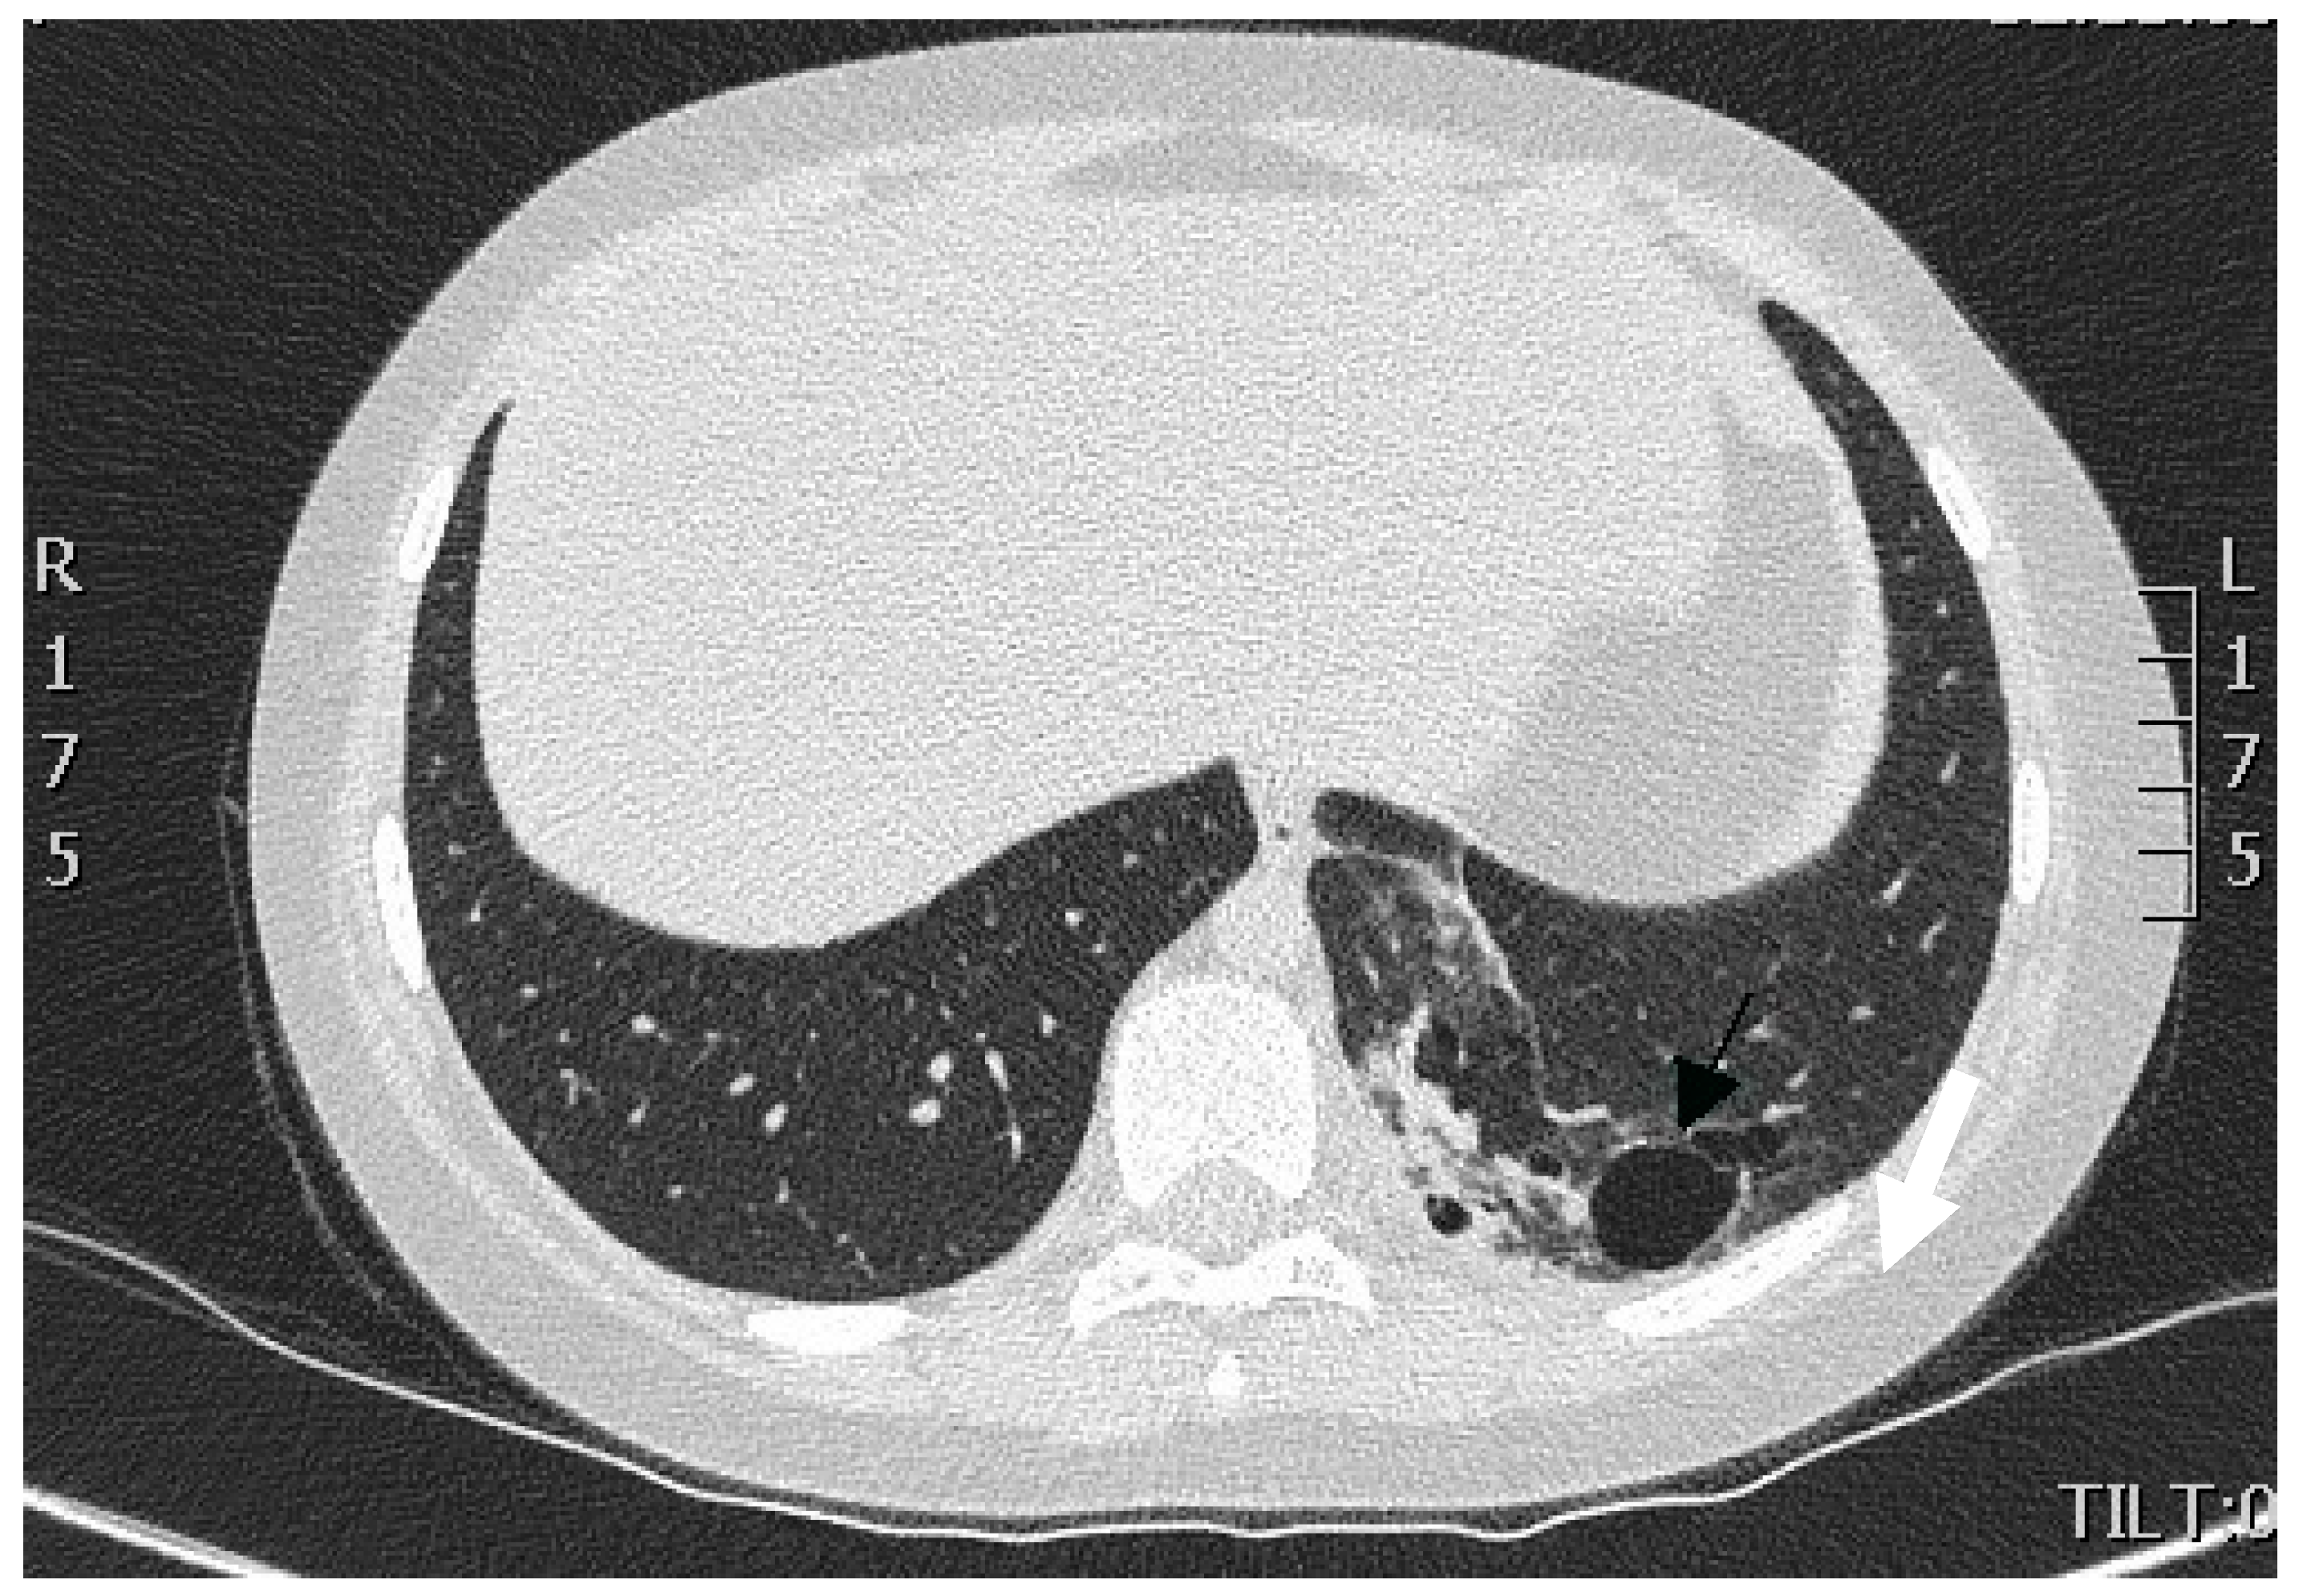

We performed multi-slice, contrast-enhanced CT scanning of the thorax and upper abdomen with subsequent multiplanar reconstruction. The lung tissue exhibited massive infiltration with cavities measuring 3 mm to 28 mm at the posterior-basal segment S10 of the left lower lobe (Figure 1).

There was no communication of the affected lung parenchyma with bronchi of the left inferior lobe. We noted no further infiltrative changes in the remainder of the left and right lungs. Contrast-enhanced CT scanning with 3D reconstruction showed normal configuration of the thoraco-abdominal aorta, celiac trunk, and renal arteries. The celiac trunk originated from the abdominal aorta at the level of the intervertebral space Th12-L1. The systemic feeding artery (proximal diameter of 5 mm) originated from the celiac trunk. This artery supplied the pulmonary intralobar sequestration in the inferior lobe of the left lung (Figure 2a,b).

When comparing the chest CT images obtained by the regional hospital with our contrast-enhanced CT image, we noted a partial regression of dystelectatic areas within the left inferior lobe of the lung, reduced fluid within the cyst-like lesions, and reduced pleural effusion. Thus, we established the diagnosis of intrapulmonary sequestration of the inferior lobe of the left lung complicated by infection and pleural effusion.

Figure 1. CT scan of the thorax. A portion of lung tissue contained cavities (indicated by arrow) and hyperdense scar formation located in the dorsomedial part of the lower lobe of the left lung.